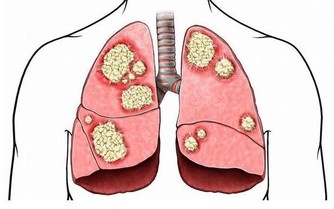

失眠已成為現代人生活中的常見問題,有些人是主動失眠,有些則是被動失眠。無論是主動還是被動,長期睡眠不好或熬夜的人,生物節律都會被打亂。睡眠不足會進一步導致交感神經興奮,人體內的兒茶酚胺類物質分泌增高,促進炎症反應,導致高血壓、冠心病、心力衰竭及心律失常等心血管疾病的發生與發展,並增加相關心血管事件的發生率。因此,失眠患者應儘早予以臨床干預,以減少其對機體的損害及各種心血管事件的發生。

失眠不僅會導致心血管疾病,對已有心血管疾病的患者,更會令病情反復發作,乃至加重,長此以往,持續高血壓還會傷害心臟與大腦,加重左心室的負擔,導致心肌肥厚,出現心臟擴大、呼吸困難等心功能不全症狀。可見,不管是健康人群還是心血管疾病患者,都需要保證充足優質的睡眠。